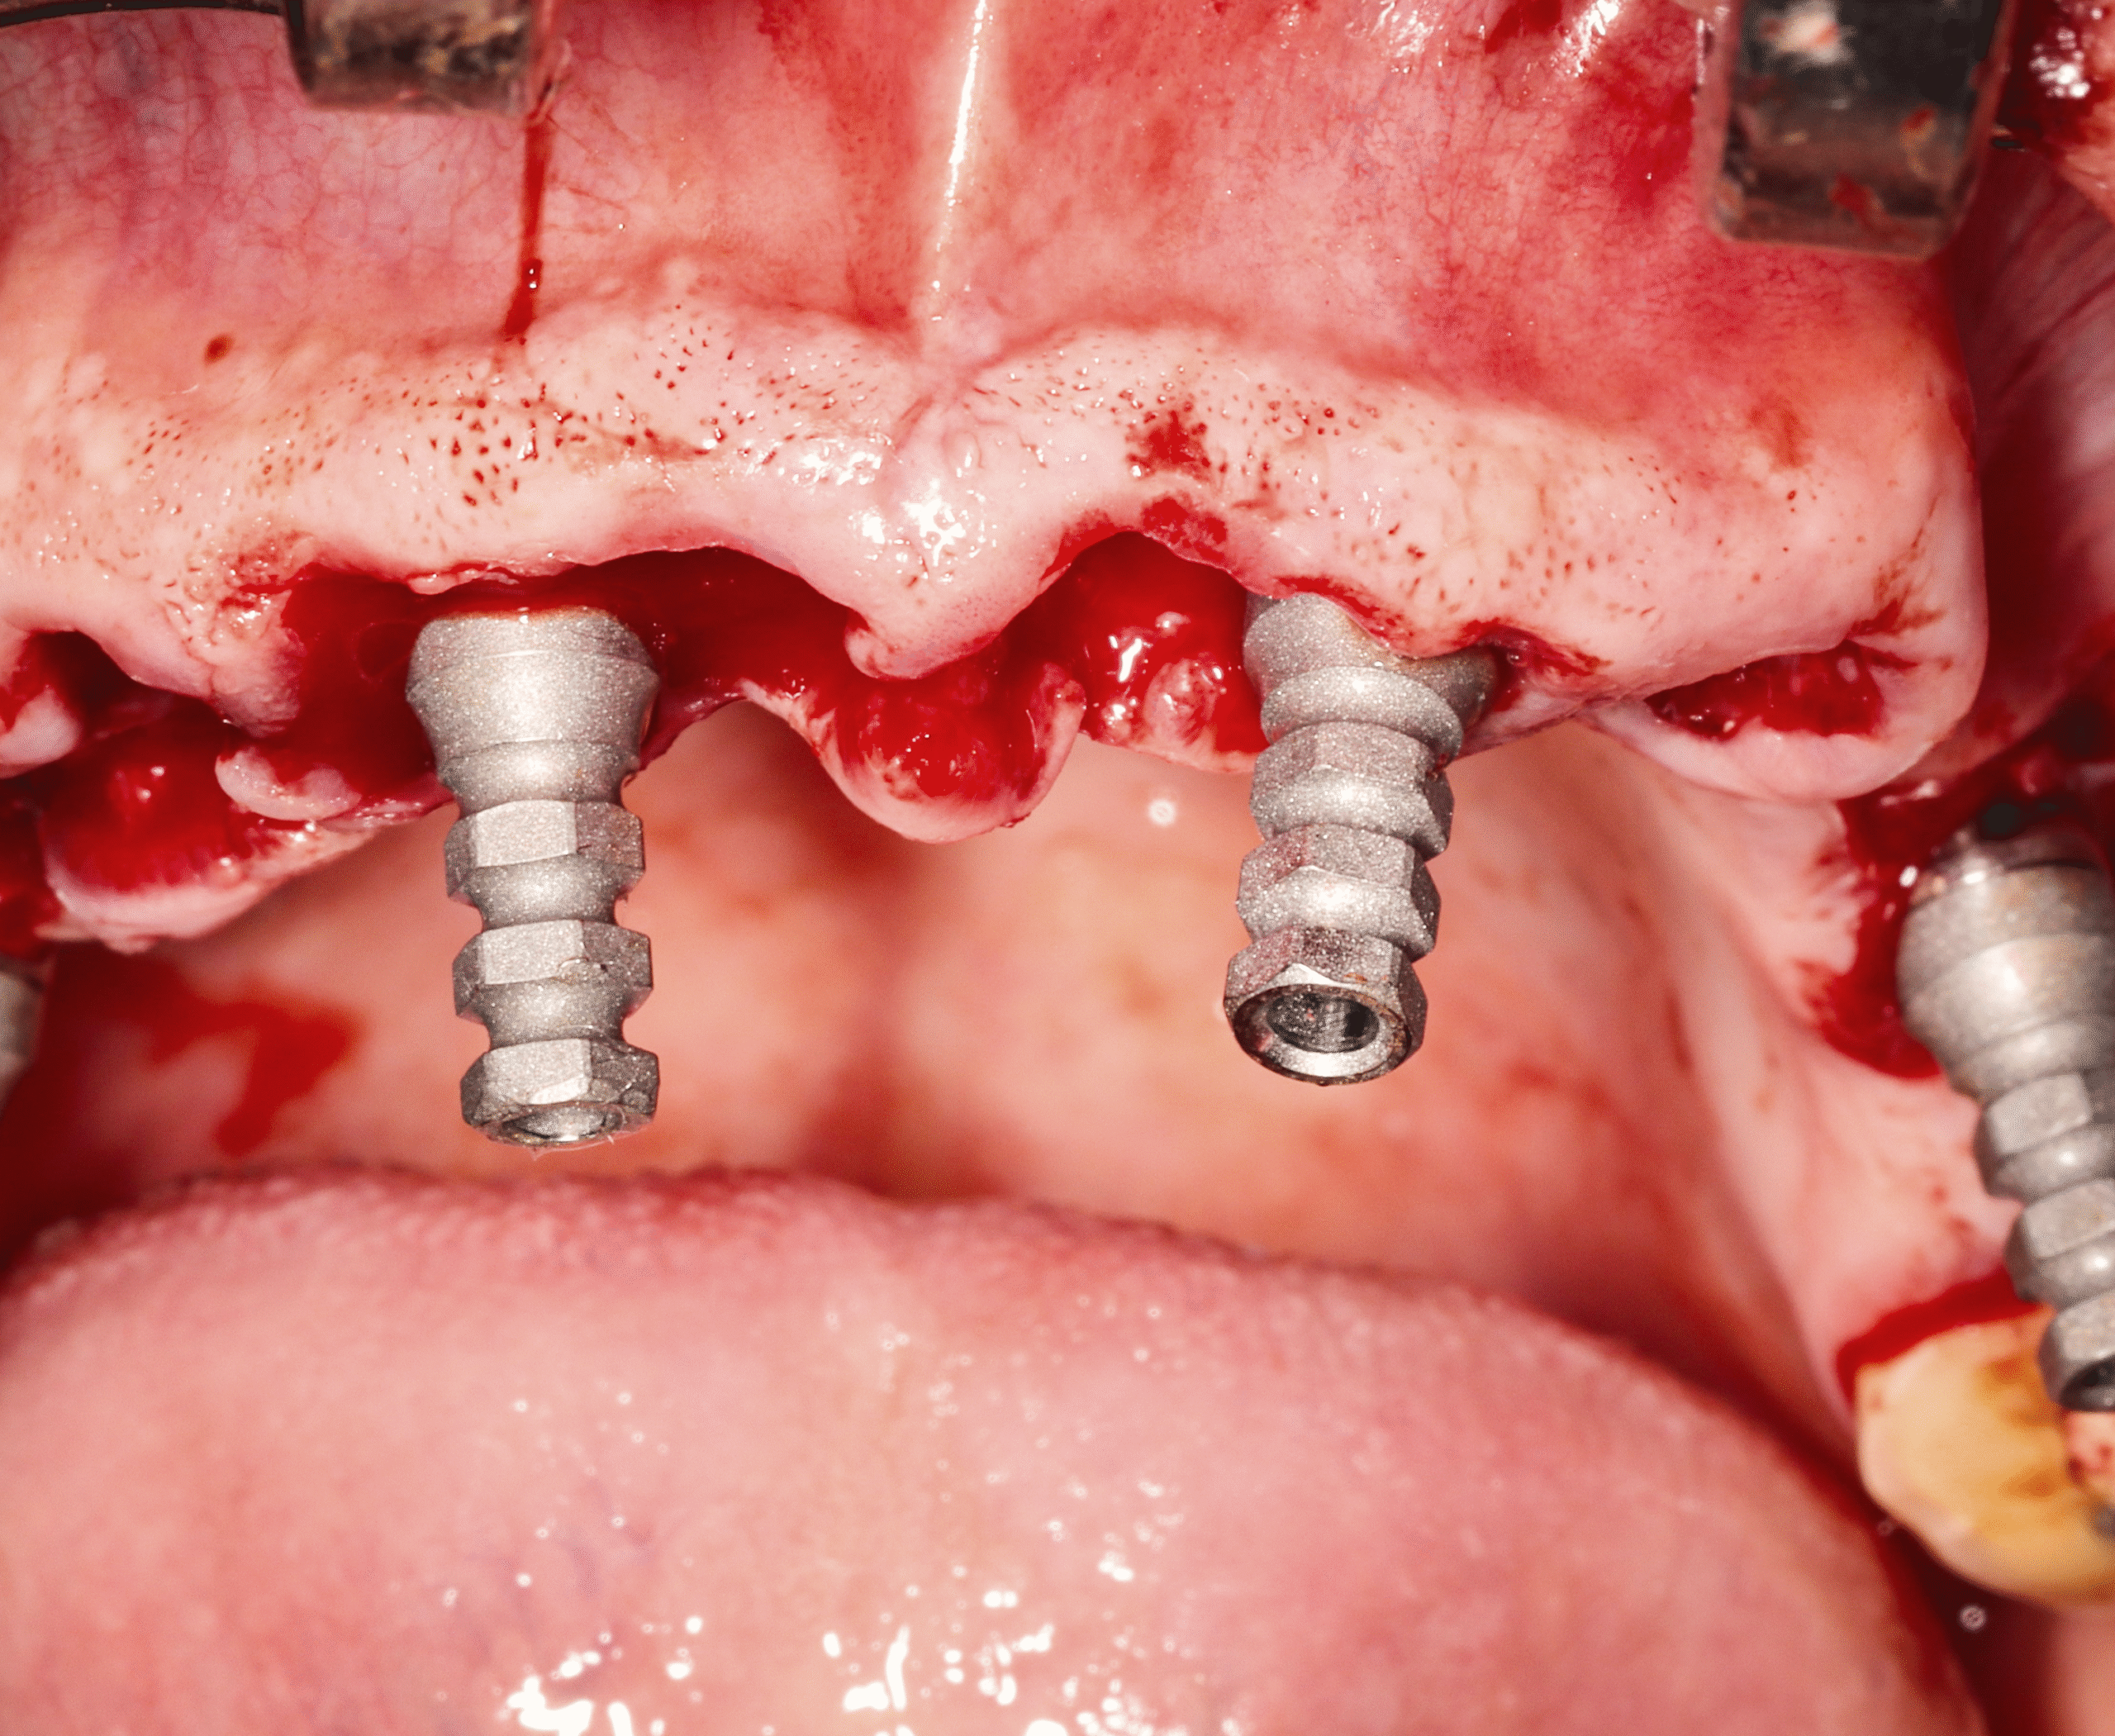

Step 3 — Strategic Implant Placement (All-on-Four)

- Placement of four implants in each arch

- Angled posterior implants used to maximize available bone without grafting

- Achieved strong primary stability suitable for immediate loading